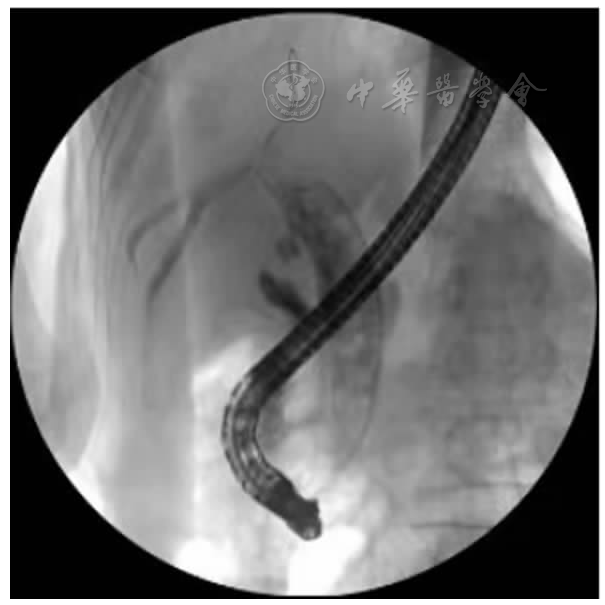

患者男,71岁。主因"右上腹痛伴黄疸1月"于2022年3月11日收入保定市第一中心医院消化内三科。患者1月前无明显诱因出现右上腹部疼痛,呈持续性钝痛,并向肩背部放射,伴发热,体温维持在37.8℃左右,以午后为重,伴寒战、皮肤及小便发黄、偶有恶心、无呕吐、体重下降约2.5 kg。既往19年前因"胆管结石"行"胆总管切开取石及胆道镜下肝内胆管取石术";1年前又因"胆囊结石"行"胆囊切除术"。入院查体:T 37.6℃、P 70次/分、R 17次/分、BP 120/80 mmHg,神志清楚、精神差、结膜无苍白、巩膜黄染、周身浅表淋巴结未触及肿大、心肺查体无异常、腹平软、上腹部可见手术疤痕,有压痛、无反跳痛及肌紧张、肝脾肋下未触及、肝区叩击痛阳性、移动性浊音阴性、肠鸣音正常。入院后辅助检查:血常规:白细胞7.70×109/L、血红蛋白117.00 g/L、血小板226.00×109/L、中性粒细胞比率72.20%;肝功:丙氨酸氨基转移酶46.60 U/L、天门冬氨酸氨基转移酶41.10 U/L、白蛋白36.90 g/L、总胆红素52.60 μmol /L、直接胆红素36.00 μmol/L、间接胆红素16.60 μmol/L、γ-谷氨酰转肽酶620.00 U/L、碱性磷酸酶337.20 U/L;肿瘤标记物:AFP 2.02 ng/ml、CEA 1.62 ng/ml、CA-19927.26 IU/ml;门诊上腹部CT提示:肝左叶体积小;胆总管下段高密度影,结石?考虑低位胆道梗阻。初步诊断:胆总管结石伴化脓性胆管炎。给予抗感染、保肝、抑酸、补液等支持治疗。于2022年3月14日经内镜中心行经内镜逆行胰胆管造影术(endoscopic retrograde cholangiopancreatography,ERCP)取石,术中泛影葡胺造影可见胆总管扩张1.2 cm,下端约见1.0 cm充盈缺损影,胆总管上段不规则充盈缺损影,肝内胆管未见异常,弓形电刀沿乳头11点方向切开约0.3 cm,1.2 cm扩张球囊扩张乳头,取石网篮取出黄褐色结石及黄白色脓性分泌物(图1),术后置入鼻胆引流管,胆汁引流通畅。术后给予暂禁食水、抑酸、补液等综合治疗。患者仍感腹痛,体温最高达38℃,术后第3天复查腹部CT示:ERCP术后改变,肝内胆管扩张;肝顶稍低密度。当时考虑患者腹痛为鼻胆管刺激所致,遂予拔除。复查血常规及肝功能较术前无明显变化,C反应蛋白:37.30 mg/L、血淀粉酶及脂肪酶正常,考虑胆管内感染脓液引流不畅,于3月21日再次行ERCP术:术中胆管造影仍提示胆总管内不规则充盈缺损影,用取石球囊取出大量黄白色脓性分泌物(图2),术毕置入8.5Fr-8 cm塑料胆管支架(图3)。术后患者腹痛仍不能缓解,并出现持续高热,体温最高达38.9℃,抗生素升级为比阿培南0.3 g,12 h 1次静脉点滴。同时口服熊去氧胆酸胶囊250 mg,每日3次,监测肝功能及炎症指标。3月24日行上腹增强CT示:肝顶多发异常强化,考虑肝脓肿可能(图6)。因治疗效果不佳,请感染性疾病科会诊后仍建议继续抗感染治疗,监测炎症指标及脓肿影像学变化,尽可能穿刺引流以缩短病程,并留取血培养以明确致病菌。遂调整比阿培南0.3 g,8 h 1次、加用莫西沙星0.4 g,每日1次联合抗感染,同时加用人血白蛋白支持对症治疗。患者腹痛及发热症状仍无明显缓解,3月31日进行上腹MRI平扫+增强检查提示为肝内多发异常信号,肝内外胆管及胆总管扩张,肝门区胆管截断,肝门区淋巴结肿大(图7)。复查腹部彩超提示肝脓肿,液化不明显,不易穿刺。于2022年4月6日加用去甲万古霉素抗感染治疗,患者治疗效果欠佳。再次请普外科会诊,仔细阅片考虑肝门区胆管截断,肝内多发不均低密度,不除外恶性肿瘤可能,建议穿刺活检。超声造影提示肝内不均质回声,倾向炎性病变,因周边血管丰富穿刺出血风险高,不宜进行穿刺活检。此时患者内科保守治疗效果不佳,恶性肿瘤不能除外,经与患者及家属反复沟通,建议手术治疗,于4月4日转入普外科并行手术探查,术中发现肝左叶萎缩、质硬,多发肿物突出肝表面,右肝未见明显肿物,腹腔广泛粘连,肝门部多发肿大淋巴结,术后病理证实为左半肝低分化胆管细胞癌(图8)。患者术后腹痛好转,体温恢复正常,家属拒绝进一步治疗,自动出院,离院后1个月病逝。

图4 3月14日ERCP下左半肝肝内胆管不显影,肝门部胆管截断